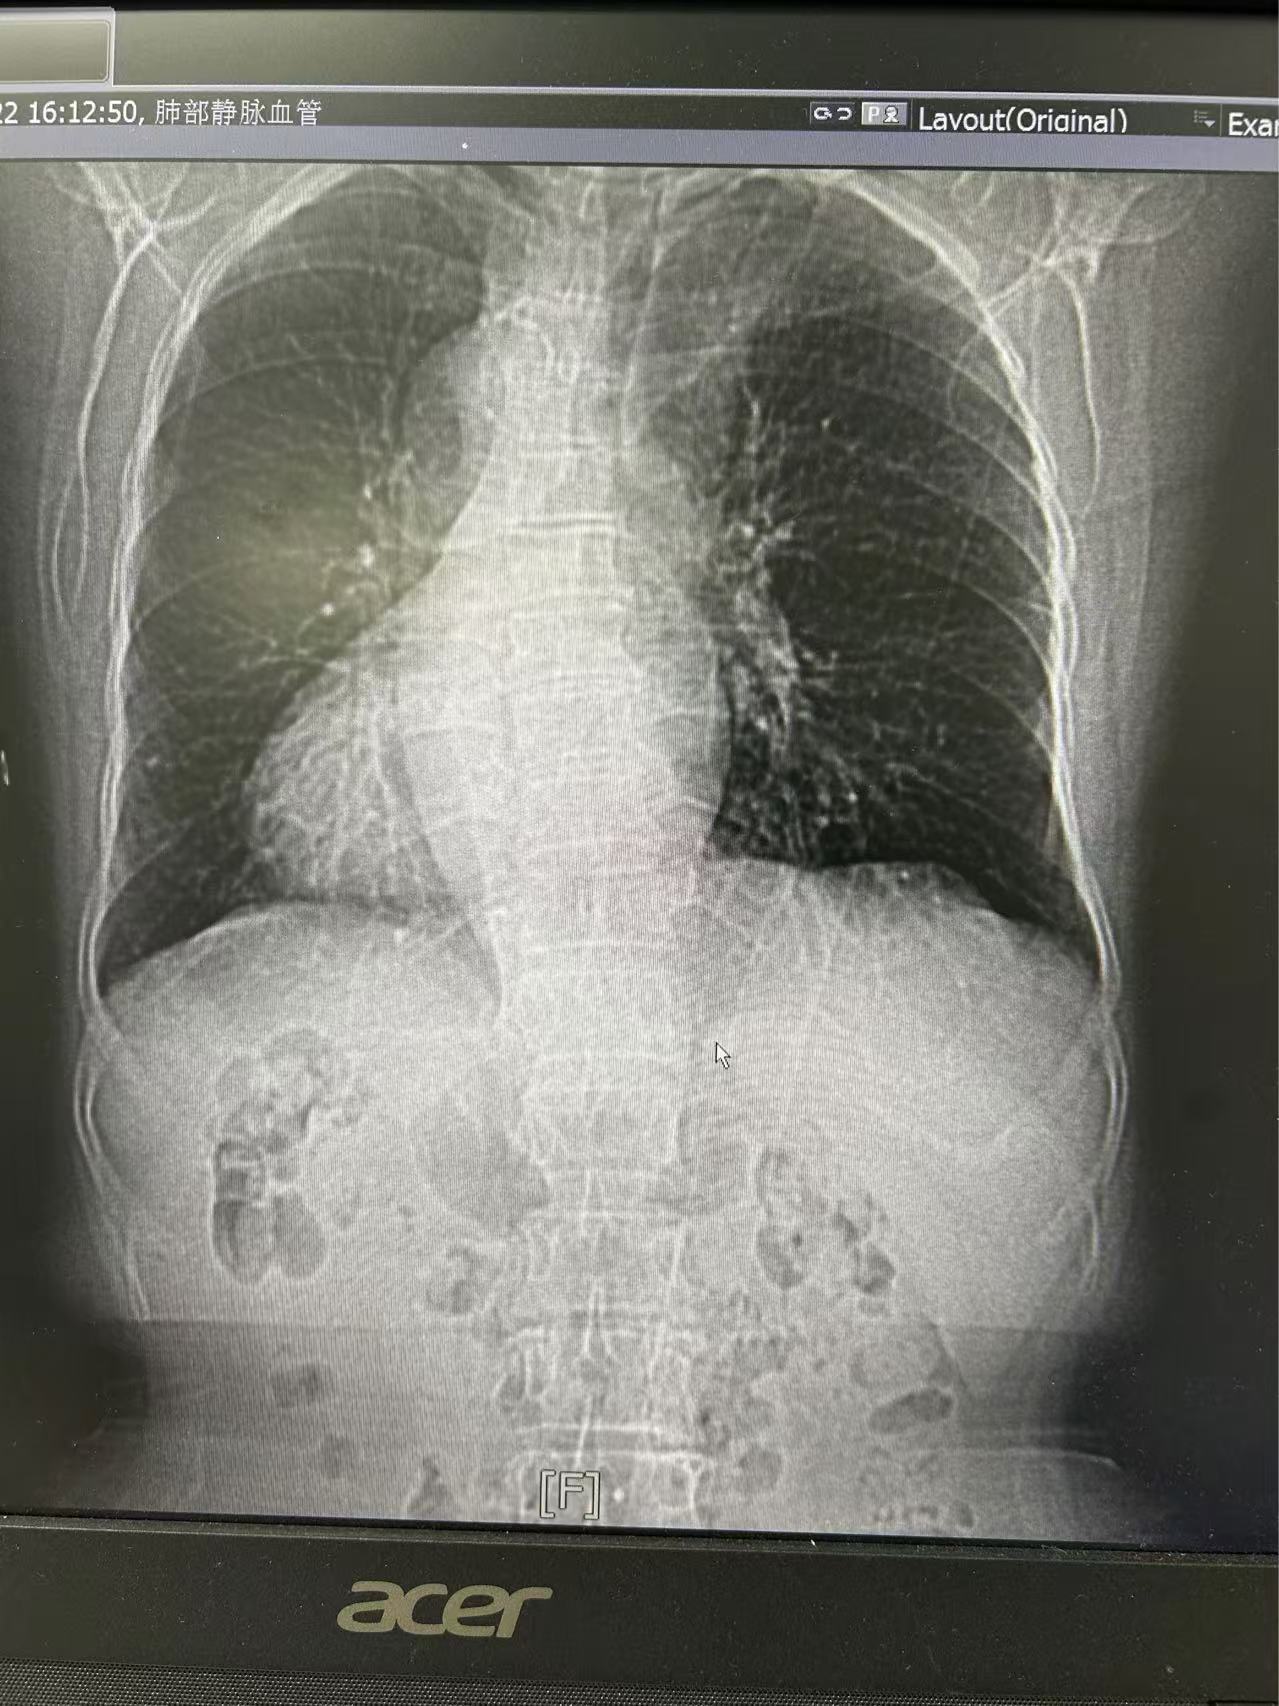

患者为老年女性,受房颤困扰40余年,并伴有镜面右位心的特殊生理结构。镜面右位心,即心脏及内脏器官位置完全反转,如同正常位置的镜像,这种罕见的先天性异常给手术治疗带来了极大的挑战。患者既往曾多次因房颤导致住院,虽经药物治疗,但病情反复,且因长期服用抗凝药物,面临严重的出血风险。

手术过程中,王洪涛教授亲自操刀,充分利用CARTO 3三维标测系统,实现了精准定位和消融,成功为患者实施了房颤射频消融术。随后,团队又克服了镜面右位心带来的操作困难,使用新一代国产左心耳封堵器LACbes成功完成了左心耳封堵术,有效预防了卒中的发生。王洪涛教授解释:“房颤射频消融术能够消除房颤的症状,而左心耳封堵术则能够闭合房颤患者血栓发生的根源部位,两者结合能够大大降低患者的卒中和出血风险。”